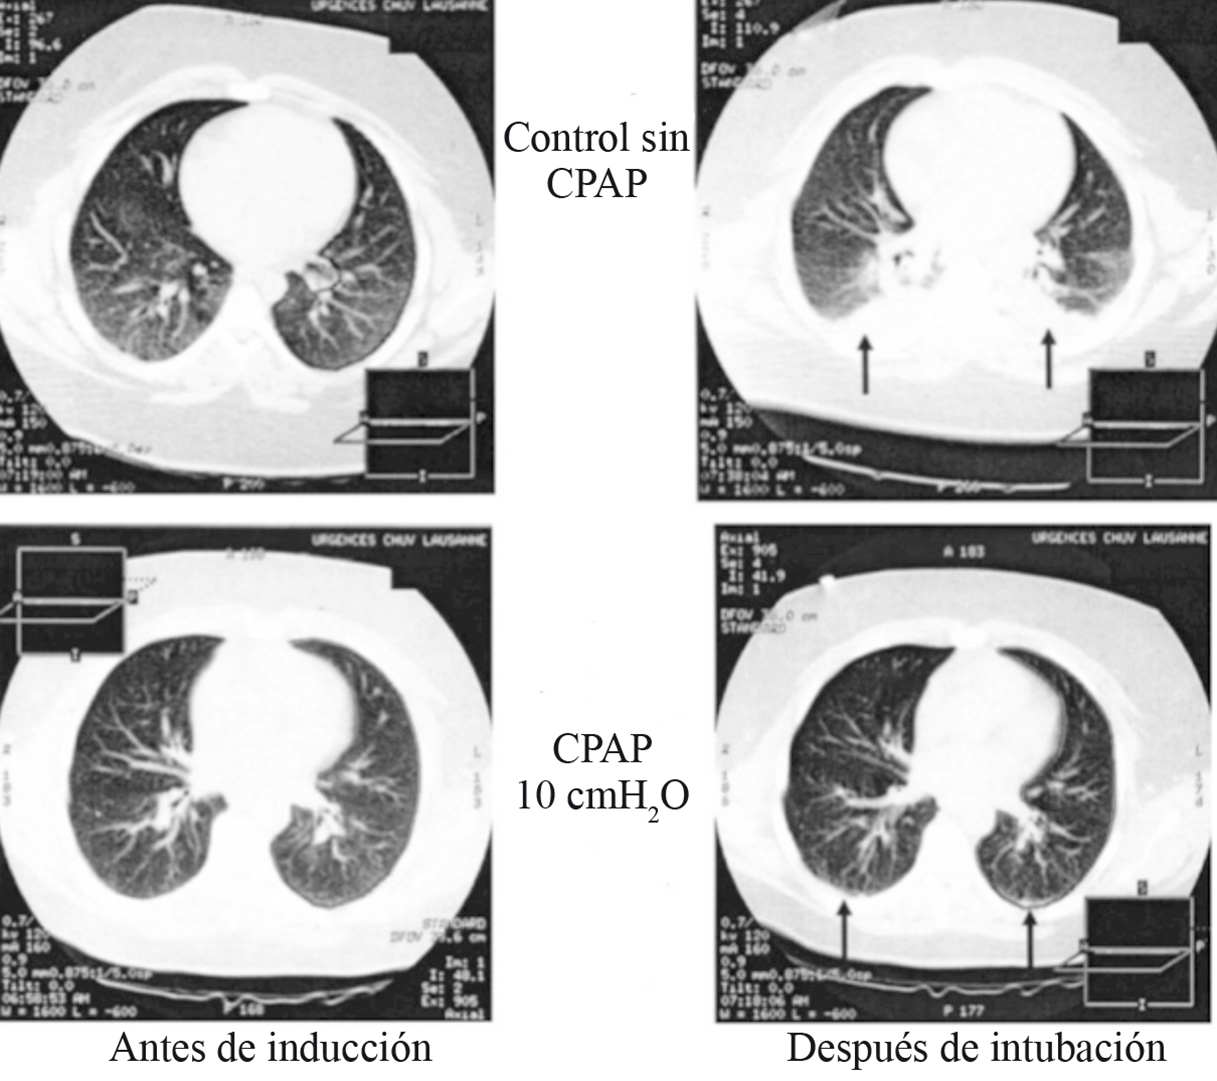

Las estrategias ventilatorias para prevenir el colapso pulmonar pueden iniciarse desde la inducción anestésica, especialmente en poblaciones de riesgo. Se ha utilizado presión positiva continua en la vía aérea (CPAP) durante la inducción anestésica para aminorar la disminución de la CRF y mantener la presión transpulmonar por encima de la presión de cierre. En un estudio realizado en pacientes con peso normal, el uso de 6 cm de H2O de CPAP durante la inducción anestésica redujo la formación de atelectasias medidas por tomografía axial computarizada (TAC) 9 . El trabajo fue repetido en pacientes obesos mórbidos, con 10 cm de H2O de CPAP, demostrando una disminución de las áreas de atelectasias de 10,4% del tejido pulmonar en el grupo control a 1,7% en el grupo de CPAP 55 (Figura 5). A pesar de sus potenciales beneficios, estas maniobras no son fácilmente aplicables o pueden estar contraindicadas en pacientes con riesgo de regurgitación, además de que su efecto se pierde rápidamente durante la laringoscopia.

Figura 5 Imágenes de tomografías computarizadas torácicas de 2 pacientes obesos mórbidos manejados con y sin CPAP durante la inducción anestésica. Se observa que en el paciente manejado con CPAP existe menor porcentaje de atelectasias que en el control. . Las imágenes fueron obtenidas 1 cm sobre el nivel del diafragma derecho. Las flechas muestran las zonas de atelectasias (Modificado de Coussa M et al, Anesth Analg 2004; 98: 1492-1495 55 ).